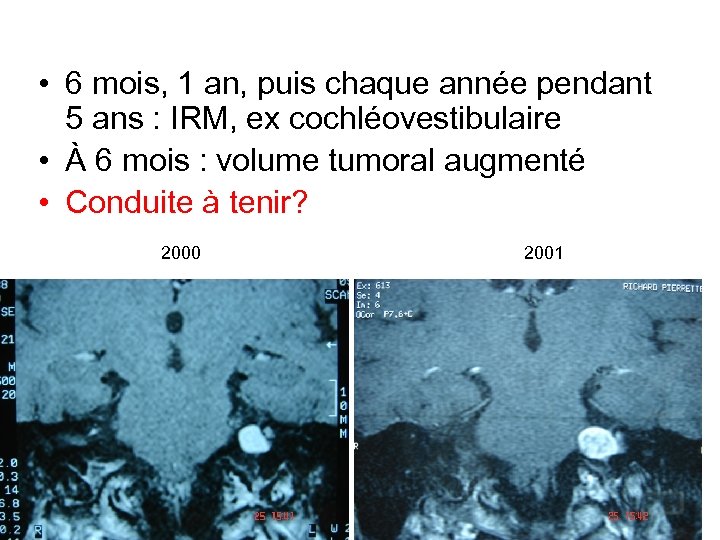

• 6 mois, 1 an, puis chaque année pendant 5 ans : IRM, ex cochléovestibulaire • À 6 mois : volume tumoral augmenté • Conduite à tenir? 2000 2001

• 6 mois, 1 an, puis chaque année pendant 5 ans : IRM, ex cochléovestibulaire • À 6 mois : volume tumoral augmenté • Conduite à tenir? 2000 2001

Conduite à tenir? • Nécrose centro tumorale post radique • À surveiller 2000 2001

Conduite à tenir? • Nécrose centro tumorale post radique • À surveiller 2000 2001